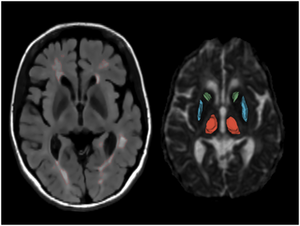

Publication: PLoS One. 2015 Dec 29;10(12):e0145493. PMID: 26713760 | PDF Authors: Esterhammer R, Seppi K, Reiter E, Pinter B, Mueller C, Kremser C, Zitzelsberger T, Nocker M, Scherfler C, Poewe W, Schocke M. Institution: Department of Radiology, University Hospital, Innsbruck Medical University, Innsbruck, Austria. Background/Purpose: The purpose of the present study was to evaluate the potential of multimodal MR imaging including mean diffusivity (MD), fractional anisotropy (FA), relaxation rates R2 and R2* to detect disease specific alterations in Parkinson's Disease (PD). We enrolled 82 PD patients (PD-all) with varying disease durations (≤5 years: PD≤5, n = 43; >5 years: PD>5, n = 39) and 38 matched healthy controls (HC), receiving diffusion tensor imaging as well as R2 and R2* relaxometry calculated from multi-echo T2*-weighted and dual-echo TSE imaging, respectively. ROIs were drawn to delineate caudate nucleus (CN), putamen (PU), globus pallidus (GP) and substantia nigra (SN) on the co-registered maps. The SN was divided in 3 descending levels (SL 1-3). The most significant parameters were used for a flexible discrimination analysis (FDA) in a training collective consisting of 25 randomized subjects from each group in order to predict the classification of remaining subjects. PD-all showed significant increases in MD, R2 and R2* within SN and its subregions as well as in MD and R2* within different basal ganglia regions. Compared to the HC group, the PD≤5 and the PD>5 group showed significant MD increases within the SN and its lower two subregions, while the PD≤5 group exhibited significant increases in R2 and R2* within SN and its subregions, and tended to elevation within the basal ganglia. The PD>5 group had significantly increased MD in PU and GP, whereas the PD≤5 group presented normal MD within the basal ganglia. FDA achieved right classification in 84% of study participants. Micro-structural damage affects primarily the SN of PD patients and in later disease stages the basal ganglia. Iron contents of PU, GP and SN are increased at early disease stages of PD. Funding:

The regions-of-interest (ROIs) were manually drawn by an experienced radiologist by using the b 1000 images, averaged for all measured directions, the FA maps and the proton-density weighted images. For that purpose, the maps of ADC, FA, R2 and R2* as well as the proton-density weighted images were first co-registered. The ROIs were segmented by syncing the b 1000 images, averaged for all measured directions, the FA maps and the proton-density weighted images in ImageJ. The ROIs were stored in the ROI manager and transferred to the co-registered maps. The segmented brain regions were highlighted in different colors: CN—black; PU—red; GP—green; TH—white; SN—blue; CC—cyan. The diffusion-weighted images, the R2 and R2*-weighted maps were transferred to the 3D Slicer software in order to co-register the R2 and the R2* maps as well as the MD and the FA maps |

Automatic Classification of Prostate Cancer Gleason Scores from Multiparametric Magnetic Resonance Images

Publication: Proc Natl Acad Sci U S A. 2015 Nov 17;112(46):E6265-73. PMID: 26578786 | PDF Authors: Fehr D, Veeraraghavan H, Wibmer A, Gondo T, Matsumoto K, Vargas HA, Sala E, Hricak H, Deasy JO. Institution: Department of Medical Physics, Memorial Sloan Kettering Cancer Center, New York, NY, USA. Background/Purpose: Noninvasive, radiological image-based detection and stratification of Gleason patterns can impact clinical outcomes, treatment selection, and the determination of disease status at diagnosis without subjecting patients to surgical biopsies. We present machine learning-based automatic classification of prostate cancer aggressiveness by combining apparent diffusion coefficient (ADC) and T2-weighted (T2-w) MRI-based texture features. Our approach achieved reasonably accurate classification of Gleason scores (GS) [Formula: see text] vs. [Formula: see text] and [Formula: see text] vs. [Formula: see text] despite the presence of highly unbalanced samples by using two different sample augmentation techniques followed by feature selection-based classification. Our method distinguished between GS [Formula: see text] and [Formula: see text] cancers with 93% accuracy for cancers occurring in both peripheral (PZ) and transition (TZ) zones and 92% for cancers occurring in the PZ alone. Our approach distinguished the GS [Formula: see text] from GS [Formula: see text] with 92% accuracy for cancers occurring in both the PZ and TZ and with 93% for cancers occurring in the PZ alone. In comparison, a classifier using only the ADC mean achieved a top accuracy of 58% for distinguishing GS [Formula: see text] vs. GS [Formula: see text] for cancers occurring in PZ and TZ and 63% for cancers occurring in PZ alone. The same classifier achieved an accuracy of 59% for distinguishing GS [Formula: see text] from GS [Formula: see text] occurring in the PZ and TZ and 60% for cancers occurring in PZ alone. Separate analysis of the cancers occurring in TZ alone was not performed owing to the limited number of samples. Our results suggest that texture features derived from ADC and T2-w MRI together with sample augmentation can help to obtain reasonably accurate classification of Gleason patterns. Funding:

|

Example of (A) a GS 6(3+3) tumor and (B) a GS 9(4+5) tumor. The top row shows the ADC image with the computed energy and entropy values overlaid on the tumor. The bottom row shows the T2-w MR image with the computed energy and entropy values overlaid on the same tumor on the corresponding slice. The texture features were computed per voxel by using a 5×5×5 patch centered at each voxel. Tumors and normal structures were identified and volumetrically segmented on both the T2-w and ADC MR images using 3D Slicer. |